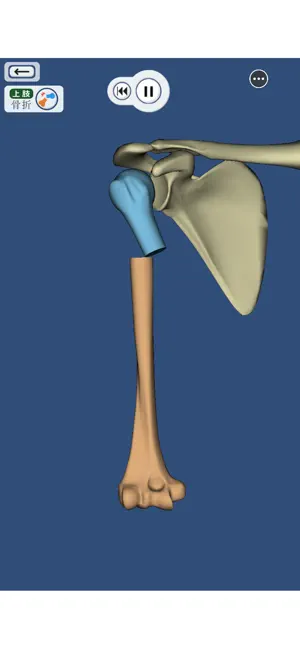

上肢、下肢の骨折と脱臼を3DCGのモデルとアニメーションで再現した骨折と脱臼を学ぶアプリ。

書籍や図譜では分かりにくかった骨折・脱臼の発生機転や転位が立体的に理解できます。

・上肢・下肢の骨折・脱臼を360°好きなアングルで!

・骨折・脱臼の発生機転をCGアニメーションで再現